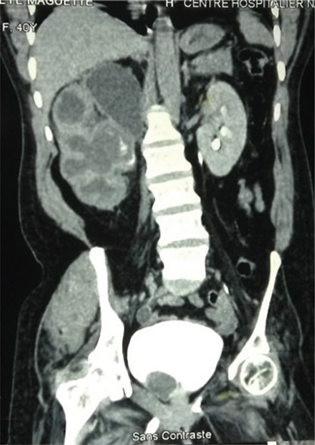

History and physical exam are important components of assessing a renal mass. The relevant clinical presentation including hematuria, flank pain, and lumbar mass should be ascertained. All possible risk factors or etiologies should be sought. Physical exam findings of varicocele or pedal edema could depict vascular involvement of the tumor or inferior vena cava (IVC) invasion. Though most authors reported the clinical triad of RCC, the presence of a lumbar mass was reported in all the studies reviewed from the sub-Saharan region (1020). A complete blood count (CBC), renal function (creatinine, estimated glomerular filtration rate), liver function (alanine transaminase, aspartate aminotransferase), and bony markers (alkaline phosphatase, calcium) should be evaluated (1, 9). In the presence of an elevated creatinine, a renal scintigraphy should be performed to assess renal function. Computed tomographic scan (CT-scan) is the imaging of choice with about 90% accuracy for renal masses (Figures 1 and 2). Renal malignancy is most likely when contrast attenuation of 10–20 Hounsfield Unit (HU) is obtained for a renal mass (9). CT scan is essential for staging renal cancer, lymph node assessment, as well as identification of metastasis. A chest CT is ideal for assessing metastasis when findings of chest x-ray are equivocal. Magnetic resonance imaging (MRI) and Doppler ultrasound are useful for determining the IVC involvement. Findings by Tengue et al., Tijani et al., Avokoudjo et al. and Salako et al. highlighted the use of CT-scan and ultrasound to diagnose and stage renal malignancies. The use of intravenous urogram (IVU) though limited was reported by some studies (12, 15, 19, 20) from the sub-Saharan region. It may have been useful for large tumors that may have distorted the renal parenchyma.

Fig 1

Figure 1: A contrast coronal CT-scan showing a hyper vascularized right T4 renal tumor found to have affected the renal vein, IVC, and inferior margin of the liver.